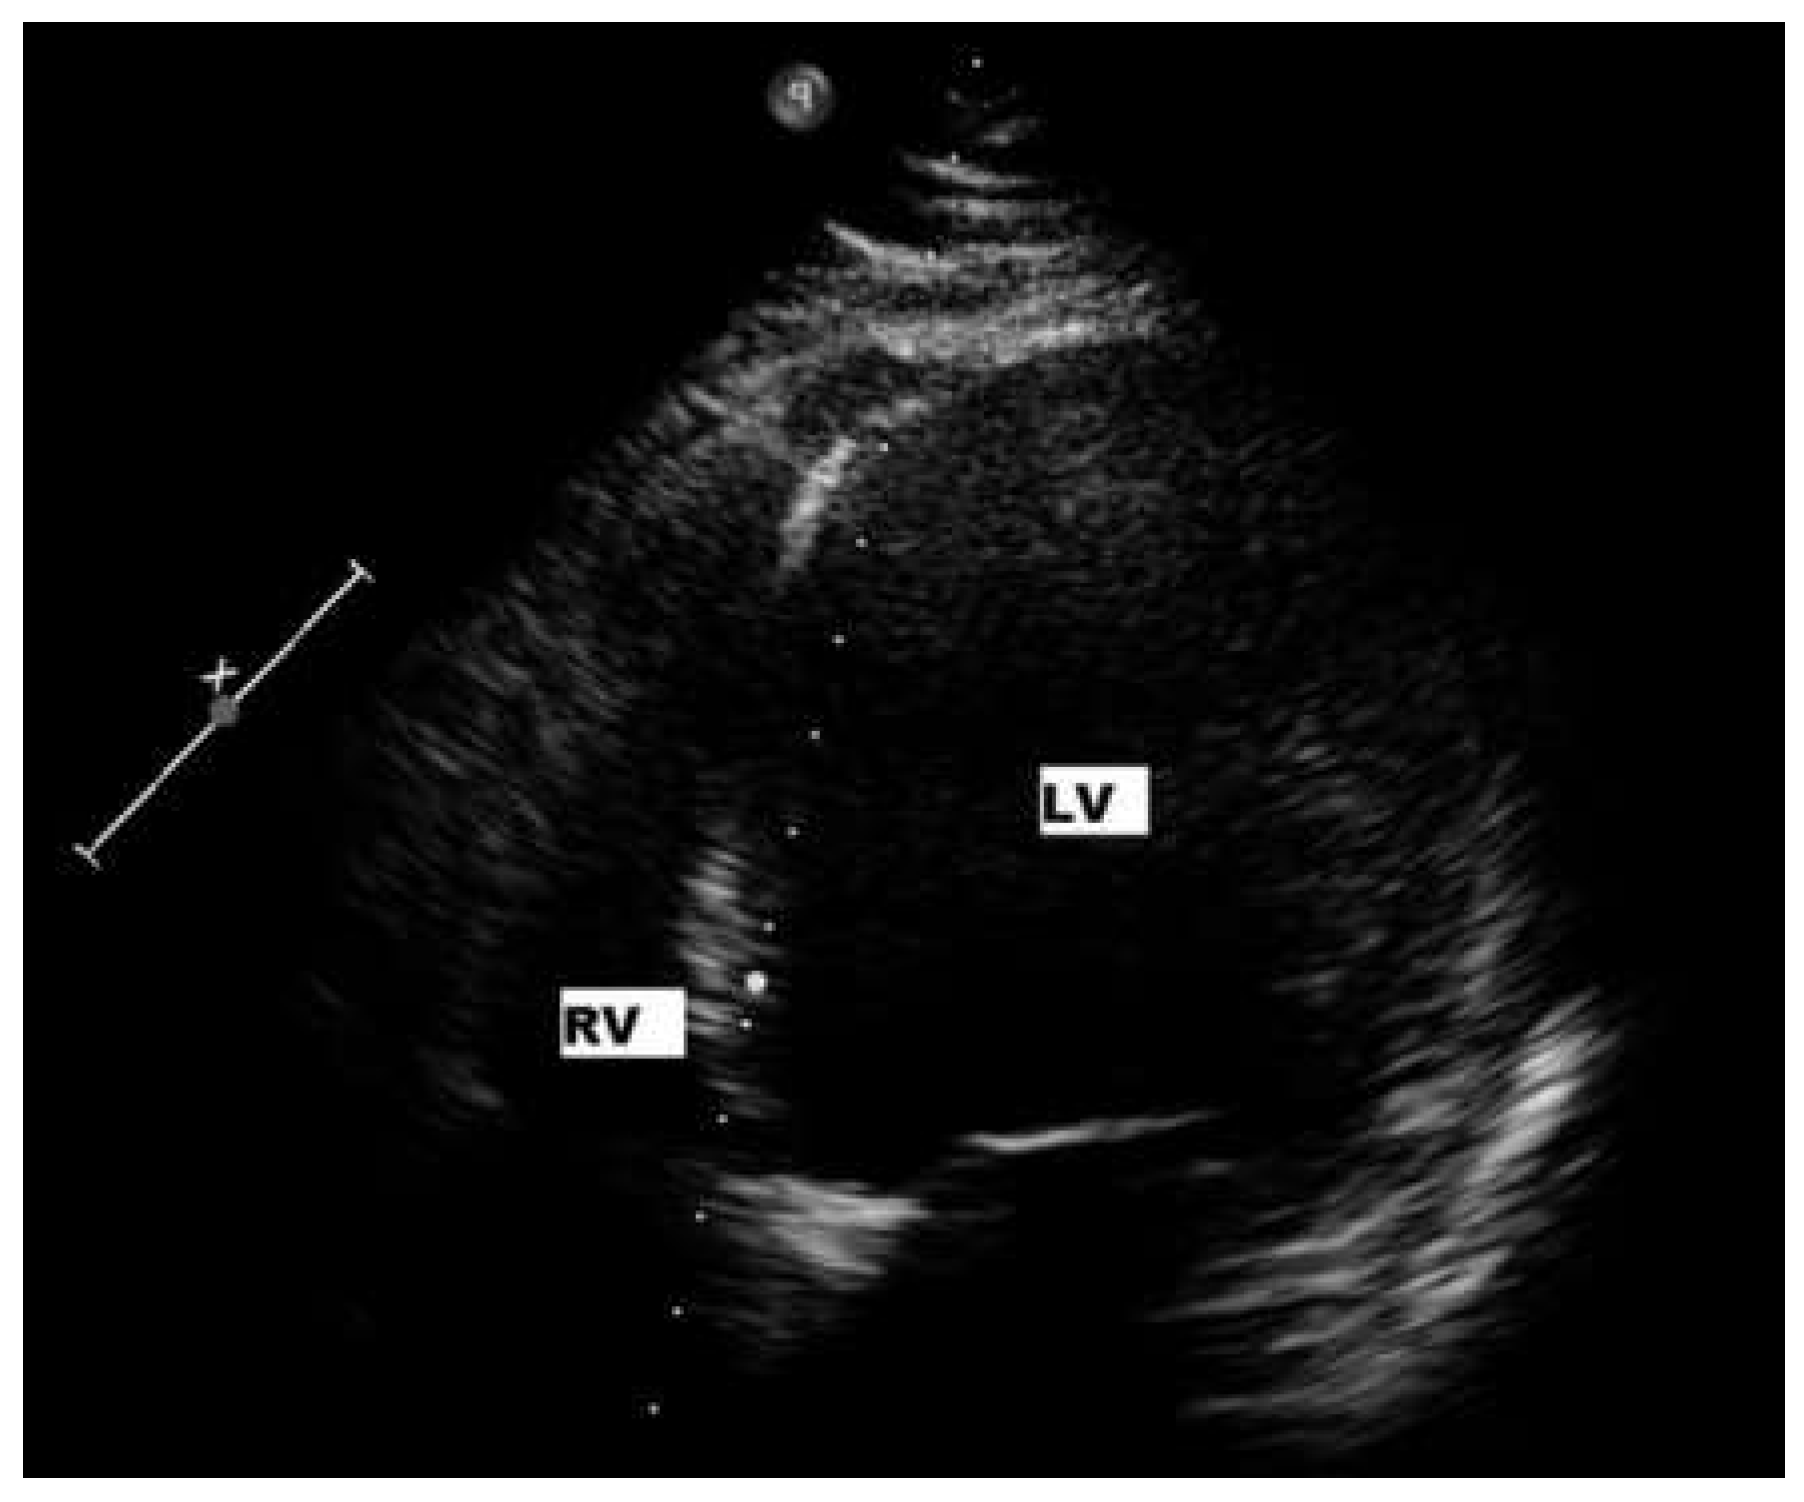

Six-month follow-up

Sixteen-month follow-up